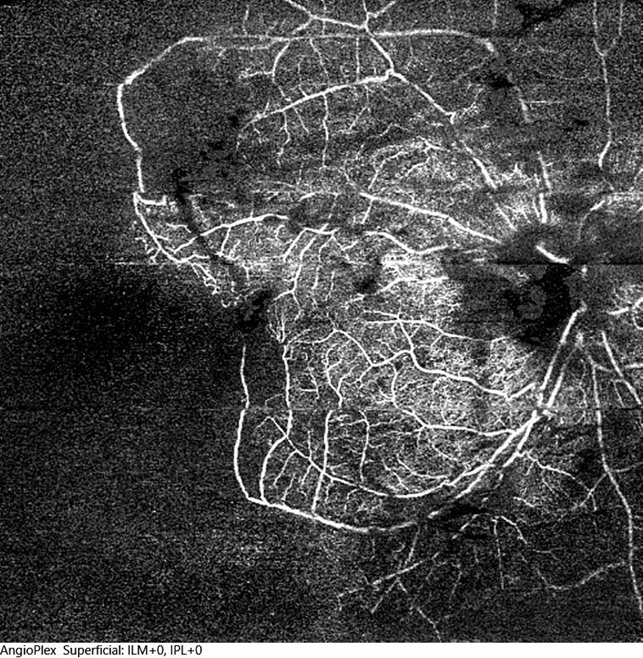

- optical coherence tomography (OCT), central retinal vein occlusion (CRVO), ischemic CRVO, ultra-wide field imaging

- 12x12 mm OCT angiogram of the right eye of a 36-year-old male who had an ischemic CRVO following a hypertensive emergency secondary to consumption of high doses of cocaine. Areas of non perfusion are found within the posterior pole and ischemia extends temporally to the mid-periphery.